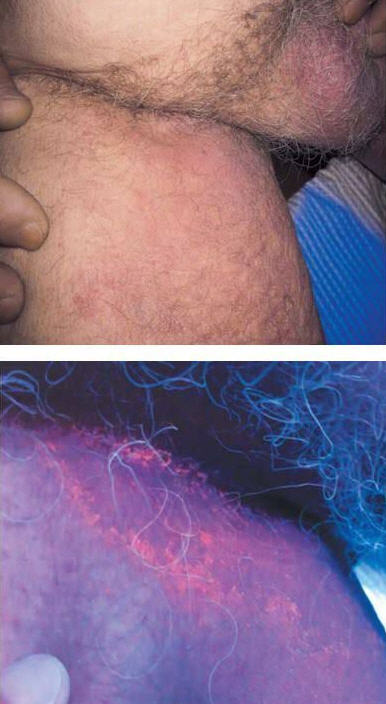

SCABİES (UYUZ)

Uyuz; Sarcoptes scabiei var. Hominis adı verilen akarın (böcek) sebep olduğu tüm dünyada yaygın olarak görülen bir hastalıktır.

Uyuz böceği deride tüneller açarak bu tünellerin içinde yaşar.

İlk defa uyuza yakalanan bir kişide belirtilerin başlaması 2-6 hafta kadar sürebilir. Ancak daha önce uyuza yakalanan bir kişide, belirtiler genellikle maruz kaldıktan 1-4 gün içinde ortaya çıkar. Hastalık belirtilerinin başlamadığı bu dönemlerde bile kişi uyuzu başkalarına bulaştırabilir.

Uyuzun en önemli belirtisi şiddetli gece kaşıntısıdır. Kaşıntı, kişinin yatağa girip ısınması ile artar ve kişiyi uykudan uyandırabilecek şiddette iken gündüzleri daha hafiftir. Kaşıntı genellikle el parmak araları, el bileğinin iç yüzü, bilekler, koltuk altları, dirsekler ve kasıklarda görülmekle birlikte tüm vücutta görülebilmektedir. Hastalığın en belirgin bulgusu parmaklar arasında dalgalı kirli bir çizgi halinde görülen, uyuz böceğinin içinde yaşadığı, gri beyaz renkli, 1-10 mm uzunluğundaki tünellerdir. Kişilerde özellikle geceleri artan şiddetli kaşıntı ve deride görülen içi su dolu keseciklerin görülmesi uyuz şüphesini arttırır.

CloseSCABİES (UYUZ)

Uyuz; Sarcoptes scabiei var. Hominis adı verilen akarın (böcek) sebep olduğu tüm dünyada yaygın olarak görülen bir hastalıktır.

Uyuz böceği deride tüneller açarak bu tünellerin içinde yaşar.

İlk defa uyuza yakalanan bir kişide belirtilerin başlaması 2-6 hafta kadar sürebilir. Ancak daha önce uyuza yakalanan bir kişide, belirtiler genellikle maruz kaldıktan 1-4 gün içinde ortaya çıkar. Hastalık belirtilerinin başlamadığı bu dönemlerde bile kişi uyuzu başkalarına bulaştırabilir.Uyuzun en önemli belirtisi şiddetli gece kaşıntısıdır. Kaşıntı, kişinin yatağa girip ısınması ile artar ve kişiyi uykudan uyandırabilecek şiddette iken gündüzleri daha hafiftir. Kaşıntı genellikle el parmak araları, el bileğinin iç yüzü, bilekler, koltuk altları, dirsekler ve kasıklarda görülmekle birlikte tüm vücutta görülebilmektedir. Hastalığın en belirgin bulgusu parmaklar arasında dalgalı kirli bir çizgi halinde görülen, uyuz böceğinin içinde yaşadığı, gri beyaz renkli, 1-10 mm uzunluğundaki tünellerdir. Kişilerde özellikle geceleri artan şiddetli kaşıntı ve deride görülen içi su dolu keseciklerin görülmesi uyuz şüphesini arttırır.